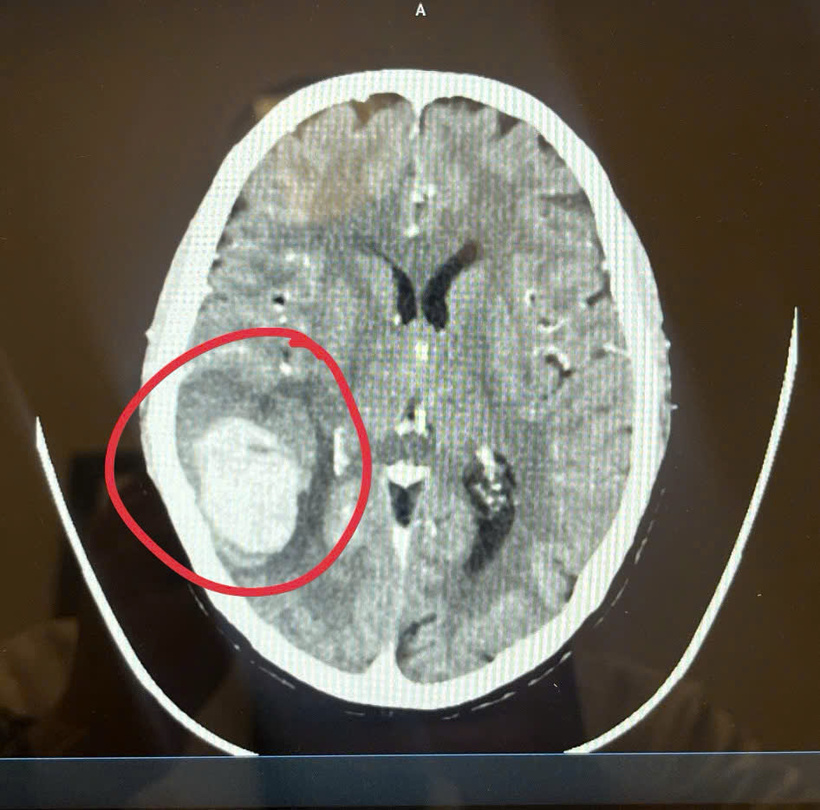

Hình ảnh khối xuất huyết não của bệnh nhân. Ảnh: BSCC

Theo bác sĩ Mạnh, khi tiếp nhận, khuôn mặt bệnh nhân méo hẳn sang một bên, nghi ngờ bị liệt dây thần kinh số 7 hoặc đột quỵ. Kết quả chụp CT cho thấy bệnh nhân bị xuất huyết não và phù. Huyết áp khi nhập viện đo được gần 200 mmHg – nguyên nhân trực tiếp gây ra cơn đột quỵ. Trước đó, bà chưa từng đi khám định kỳ dù có dấu hiệu tăng huyết áp.